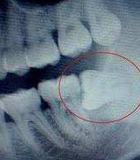

患牙拍片